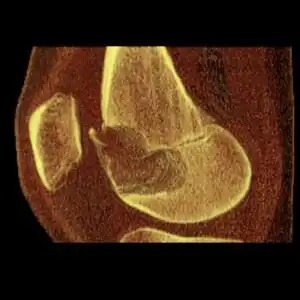

| Chondoblastoma of thigh bone near knee (CT scan, non-contrast) | |

1. b. CT scan shows chondroblastoma of thigh bone near knee more clearly -

1. c. CT scan of chondroblastoma of thigh bone near knee (cross-section view) -